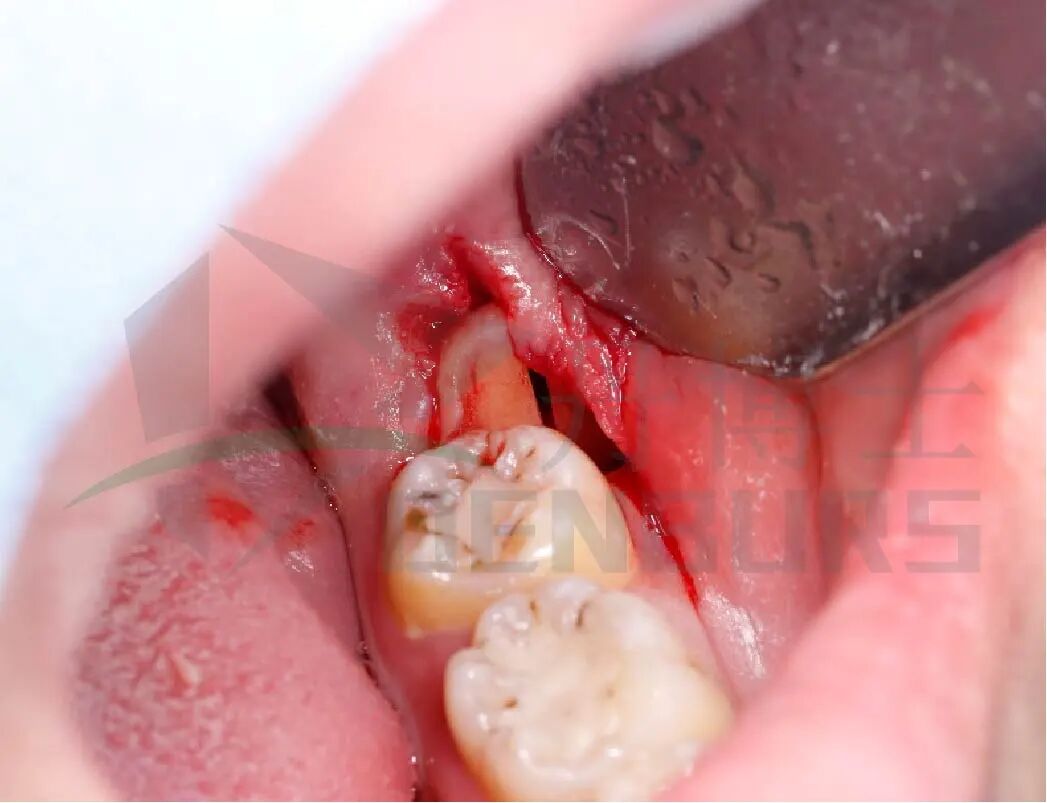

2)分冠

用丹博士C33L.317.016车针从冠根联合处(釉牙本质界)颊侧向舌侧,磨除,分冠;C33L.317.012车针分根,解除冠根阻力。